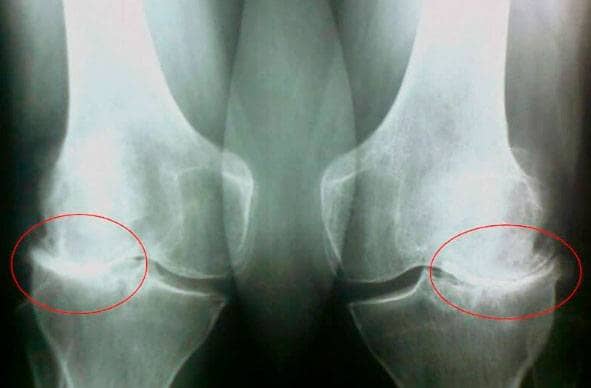

така се надявах... Без повече приказки ми направи пълен преглед, който включваше

рентгенови снимки и

изследвания на кръв и урина.

При следващото посещение, буквално в

рамките на няколко минути,

тя ми постави диагноза вторичен

остеоартрит с

усложнения. Честно казано, не разбирах какво точно казва. Обясни

Ден 35: Отидох

на преглед и ми

направиха рентгенови снимки. Никакви признаци на остеоартрит! Хрущялите в

ставите ми бяха като на

20-годишно момиче. Лекарят реши, че предишната рентгенова снимка вероятно е била

с дефект, така че

диагнозата остеоартрит е била погрешна.